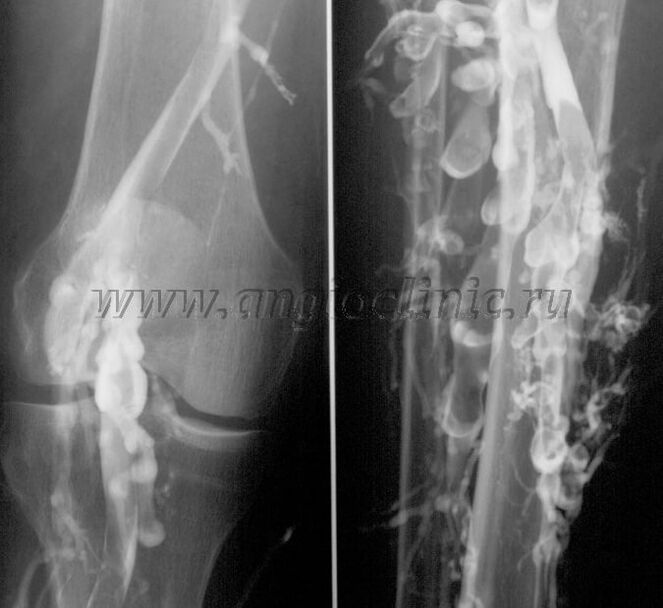

Контрастна венографија

Обично је ултразвучно скенирање довољно за потпуну дијагнозу венске патологије, али је у неким случајевима потребно проучити однос између стања дубоког и површног венског система, посебно у случају релапса проширених вена и секундарних проширених вена.

Ултразвучно скенирање

За решавање ових проблема користи се контрастни рендгенски преглед. Сафенозне вене се пунктирају и даје се контраст. Кретање контраста се посматра на монитору рендгенског апарата и врше се сви неопходни тестови и пројекције. Тренутно се венографија за проширене вене користи веома ретко.